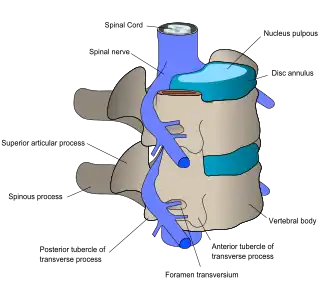

At each level of the spinal column, spinal nerves branch off from either side of the spinal cord and exit between a pair of vertebrae, to innervate a specific part of the body. The area of skin innervated by a specific spinal nerve is called a dermatome, and the group of muscles innervated by a single spinal nerve is called a myotome. The part of the spinal cord that was damaged corresponds to the spinal nerves at that level and below. Injuries can be cervical 1–8 (C1–C8), thoracic 1–12 (T1–T12), lumbar 1–5 (L1–L5),[9] or sacral (S1–S5).[10] A person's level of injury is defined as the lowest level of full sensation and function.[11] Paraplegia occurs when the legs are affected by the spinal cord damage (in thoracic, lumbar, or sacral injuries), and tetraplegia occurs when all four limbs are affected (cervical damage).[12]

Muscle function

A group of muscles innervated through a specific part of the spine is called a myotome, and injury to that part of the spinal cord can cause problems with movements that involve those muscles. The muscles may contract uncontrollably (spasticity), become weak, or be completely paralysed. Spinal shock, loss of neural activity including reflexes below the level of injury, occurs shortly after the injury and usually goes away within a day.[42] Priapism, an erection of the penis may be a sign of acute spinal cord injury.[43]

The specific parts of the body affected by loss of function are determined by the level of injury. Some signs, such as bowel and bladder dysfunction can occur at any level. Neurogenic bladder involves a compromised ability to empty the bladder and is a common symptom of spinal cord injury. This can lead to high pressures in the bladder that can damage the kidneys.[44]